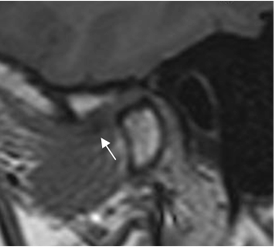

Fig 9. Disco luxado, que no reduce.

A: RM GE sagital oblicuo con boca cerrada. Disco con alteración de su morfología y señal, desplazado anteriormente.

B: RM GE sagital oblicuo con boca abierta. El disco persiste desplazado anteriormente.